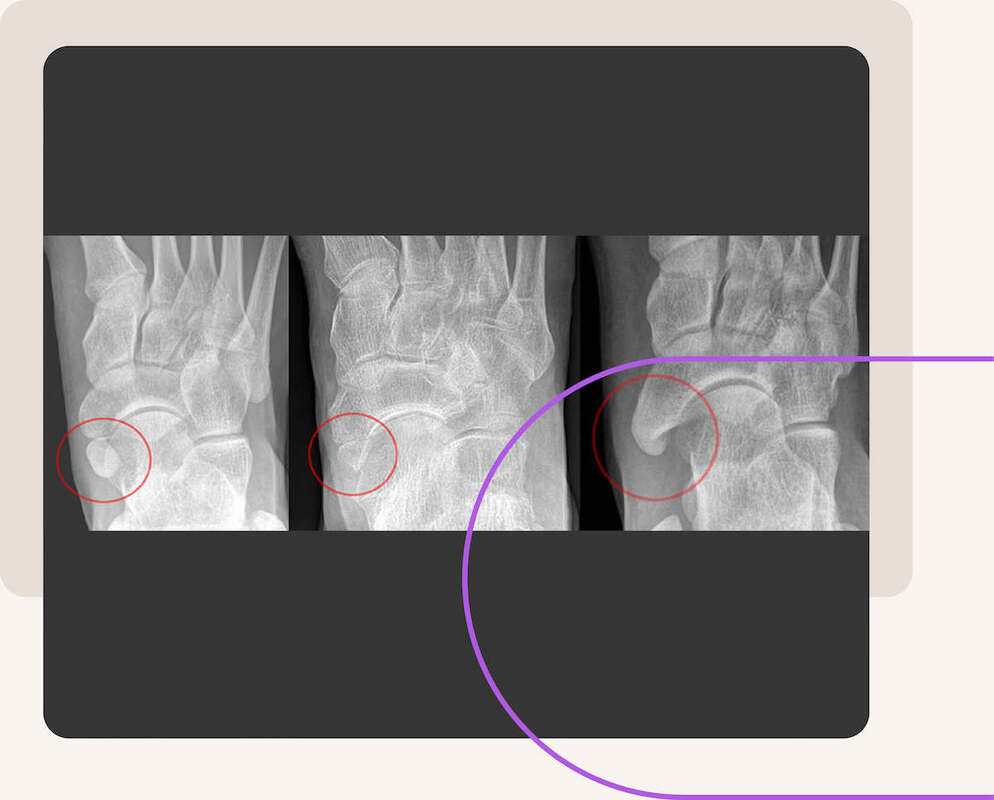

Accessoire os naviculare syndroom (extra botje op het scheepsvormig beentje)

De voet bestaat uit verschillende botten en op sommige plaatsen kunnen extra kleine botjes voorkomen (accessoire). Zo ook op het scheepsvormig beentje (os naviculare) dat zich aan de binnenzijde van de voetwortel bevindt. Accessoire os naviculare betekent letterlijk “extra bot op het scheepsvormig beentje”. Een andere benaming hiervoor is “os tibiale externum”.

Dit extra botstuk op het scheepsvormig beentje geeft vaak een bult(je) aan de binnenzijde van de voet. Dit kan in de weg zitten met het dragen van schoenen wat klachten op kan opleveren. Tussen dit extra botstuk en het scheepsvormig beentje kan het kraakbeen beschadigd raken en ook dit kan voor pijnklachten zorgen.